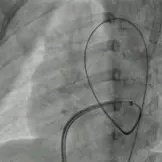

二次术中影像

建立输送轨道

建立股动脉-VSD-股静脉轨道,沿泥鳅导丝送7F输送鞘至左室,选择6mm对称型、腰高7mm全降解封堵器。

左右盘面展开并锁定

左侧伞盘出鞘为球状,牵拉成型线后形态佳,后展开右盘,封堵器呈现“长哑铃状”,主动脉瓣少量反流。

轻轻牵拉成型线使封堵器成型,牵拉后左伞盘被拉进瘤腔内。

左右盘展开后,封堵器未锁定时造影可见封堵器中间少量反流,主动脉瓣少量反流。

牵拉成型线锁定后,分流消失,主动脉瓣反流消失。

封堵器锁定后呈“蝴蝶状”明显盘状形态,室水平分流完全消失,主动脉瓣反流消失。